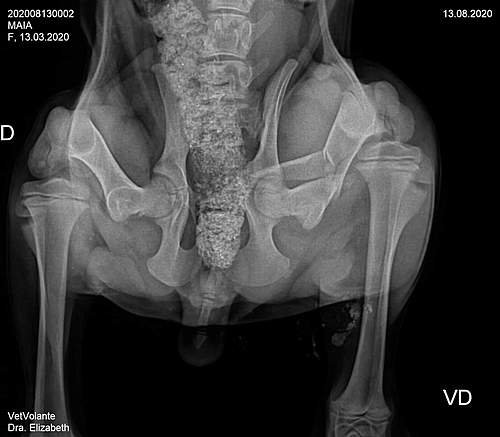

A Maia precisa de ajuda, ela foi atropelada, sofreu uma fratura na bacia e no femuor, precisa urgente de cirurgia. Ela tem dono, são duas crianças, os pais, o felizmente não tem condição que arcar com as despesas da cirurgia. A Maia tem apenas cinco meses, tem uma vida toda pela frente, mas precisa ser operada com urgência. Ela é uma cachorrinha muito dócil e muito carinhosa, as crianças sentem falta dela, é um membro da família. Que Deus abençoe cada um que fizer uma doação, ajudará a salvar a vida de uma cachorrinha.